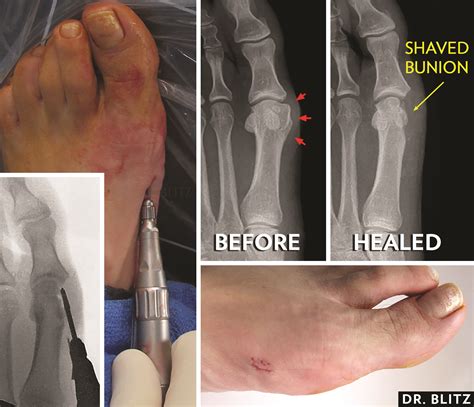

2. Exostectomy

In cases where the bunion is mild, an exostectomy, or “bunionectomy,” may be performed. This procedure involves simply removing the bony enlargement (the bump) from the joint without cutting or repositioning the bone. However, this is rarely done alone because it does not correct the underlying structural misalignment, meaning the bunion could return.

Selecting the right operation is a collaborative decision between you and your podiatric or orthopedic surgeon. Your surgeon will take X-rays to assess the degree of the angle of your big toe (hallux valgus angle) and the angle between the first and second metatarsals. They will explain which technique offers the highest probability of long-term correction based on these measurements. Do not hesitate to ask questions about the expected recovery time, potential complications, and what kind of physical limitations you might face in the months following surgery. Investing time in choosing an experienced surgeon and understanding the procedure will significantly improve your chances of returning to a pain-free, active life.